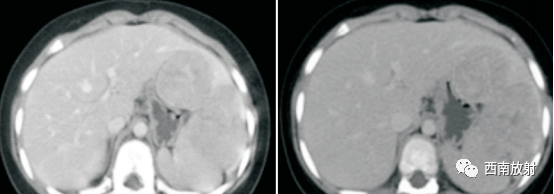

▲病例1:肝母细胞瘤:CT平扫显示肝左叶S2/3类圆形稍低密度肿块,边界模糊,增强扫描动脉期病灶显示不均匀强化、以边缘强化为主并见增粗的肝左动脉供血,门脉期及延迟期病灶强化逐渐减退。(病例来源:李钱程.儿童肝母细胞瘤的 CT诊断中表现及误诊分析[J].中国CT和MRI杂志,2020.18(11):107-109.)